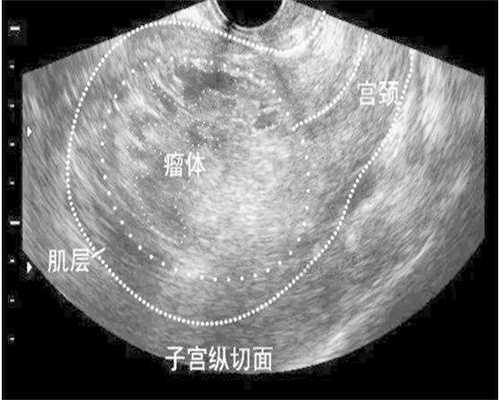

做供卵代怀的女性并不能选择人工做还是自然做,这需要医生根据你的情况来决定。人工周期移植方案是代孕婴儿方案中的一种,试管婴儿技术被认为是辅助生殖技术的一种创新,给很多没有孩子的家庭带来了可爱健康的孩子,但是作为一种技术并不是百分之百可以成功的,试管给女性也会带来一些特定的危害:

1.人工周期中的试管女性通常需要使用药物来帮助促进排卵,使一些卵子发育成熟,但在这个过程中卵巢可能会受到过度刺激,用药量也会增加高血压、高脂血症等疾病患者并发症的几率;2.为了不影响卵子的质量,在取卵时大多不进行麻醉直接进行取卵,取卵后可能会出现很大的情况回导致腹腔出血。为了不影响卵子的质量,在取卵的时候大多都是不打麻醉直接进行取卵,这样做之后可能会有很大的情况回导致腹腔出血等症状。虽然人工周期可能会对人体产生一定的伤害,但试管婴儿技术也在不断发展,相信这方面的问题也能逐步得到改善。目前,人工周期是试管中比较常用的一种方案,适合一些自然排卵困难的女性,其优点是时间好控制,不用每个月都等,一次就可以取出多个质量较好的成熟卵泡。